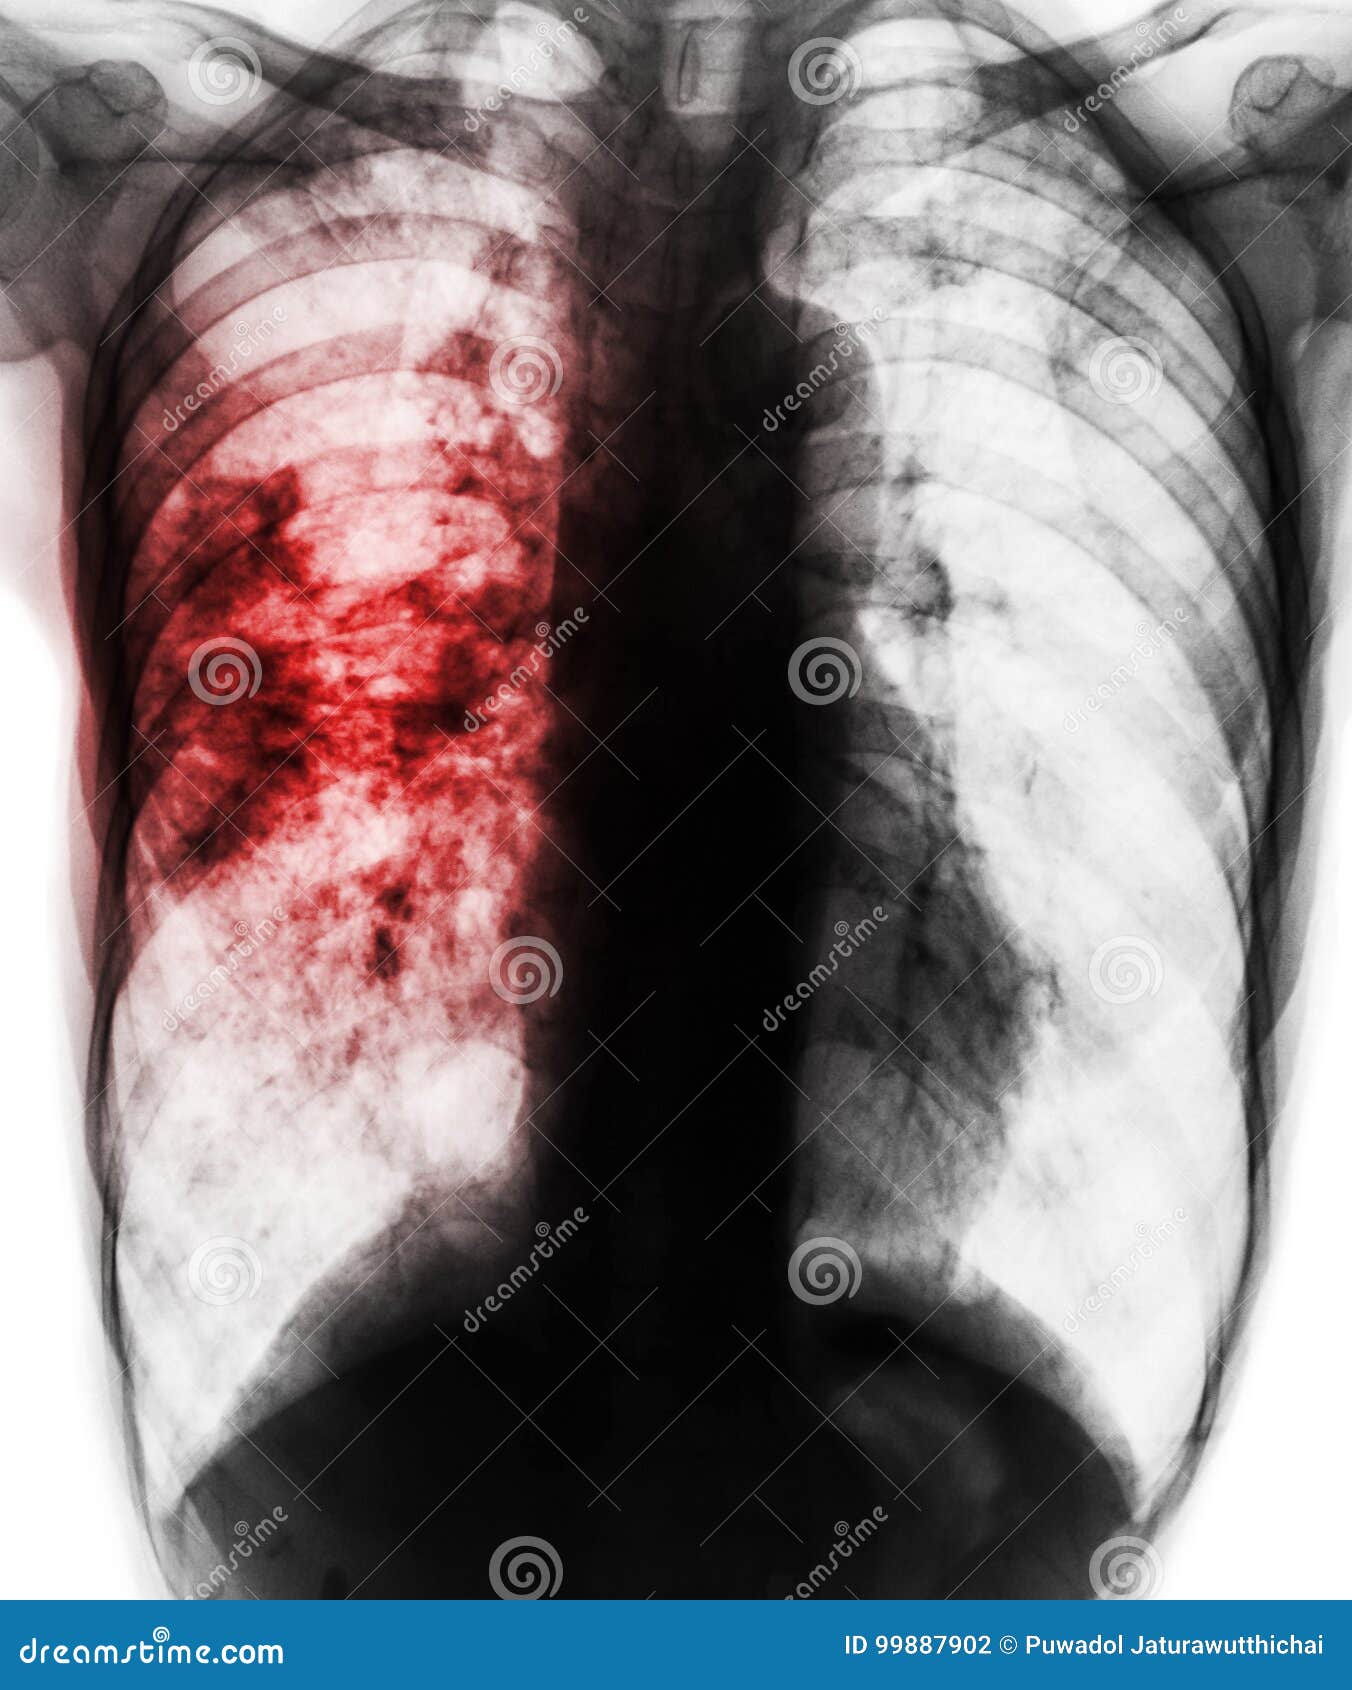

Снимок легких при туберкулезе является важным методом диагностики этого заболевания. На рентгеновских снимках можно увидеть изменения в легких, которые свойственны туберкулезу.

Очаговый туберкулез рентген

Фотографии снимков легких при туберкулезе

В данной статье представлены многочисленные фотографии снимков легких при туберкулезе, чтобы помочь вам понять, как выглядят изменения легких на рентгеновских снимках при этом заболевании.